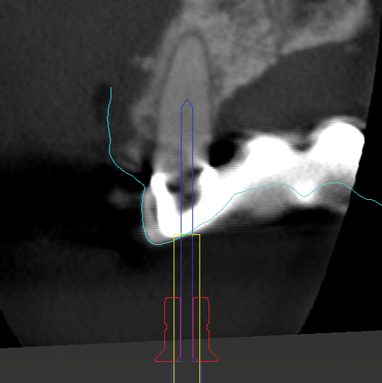

Fig 6: CBCT imaging of a maxillary lateral incisor requiring root canal treatment.

Figure 6

Fig 7: Fusion of CBCT data (shown in magenta) with the IOI (shown in cyan).

Figure 7

Fig 8: Virtual planning of the endodontic access cavity for this complex case, involving a calcified root canal in a lateral incisor that also serves as an abutment tooth for a fixed dental prosthesis.

Figure 8

Fig 9: Virtual design of a custom guide equipped with a sleeve system to direct the bur, incorporating inspection windows to ensure accurate positioning and stability of the guide on the dental arch.

Figure 9

The use of IOSs in combination with other imaging modalities, such as CBCT and 3D facial scans, is playing a crucial role in advancing treatment planning in modern dentistry. This integration enables the creation of so-called "digital twins," ie, 3D models that precisely capture anatomical details and their spatial relationships. These digital twins enhance the precision of various dental interventions. When IOI data and data from facial scans are combined, they facilitate techniques such as digital smile design.7 Additionally, digital twins generated from the integration of IOI and CBCT support both static and dynamic navigation methods.8,9 This approach is increasingly being adopted across a range of clinical applications, including dental implant placement, orthodontic mini-implant placement, and endodontic access cavity preparation (Figure 6 through Figure 9).